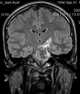

CSF-intensity brainstem lesion

A brain tumor occurs when abnormal cells form within the brain. There are two main types of tumors: cancerous (malignant) tumors and benign (non-cancerous) tumors. [Source: Wikipedia ]